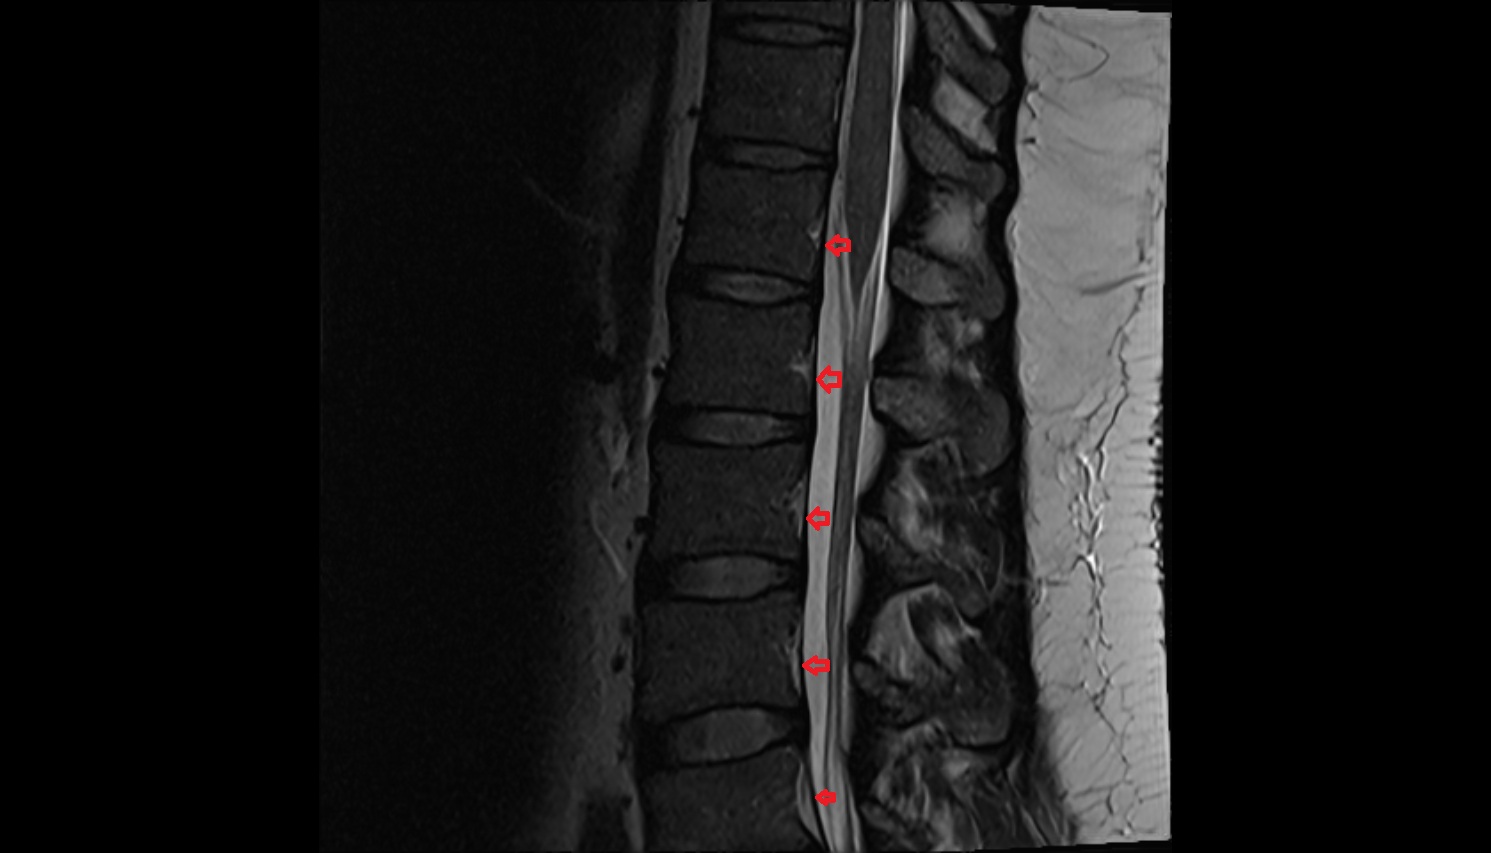

- Spinal cord

- subarachnoid space of spinal cord

- Cauda equina

- Conus medullaris

- Filum terminale internum